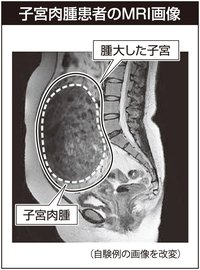

子宮肉腫は子宮内の腫瘤(りゅう)を形成しますので=画像=、子宮筋腫との区別が問題となります。子宮筋腫は良性の疾患で30歳以上の20~30%、小さな筋腫を含めると70%の女性が持つといわれています。20代の女性にも見られることがあります。子宮筋腫の半数以上が無症状で経過し、健康診断や他の病気の診察時に偶然見つかる場合もあります。つまり、子宮筋腫があることに気付かないまま過ごしている女性が多いのです。筋腫がある程度大きくなると、血液供給が追いつかなくなり変性することがあります。変性は内部が粘液腫様や脂肪様に変化したり壊死(えし)や石灰化が生じたりして、筋腫全体が不整になる現象です。ただし子宮筋腫はあくまで良性で、肉腫に変わることはありません。

超音波検査やMRIなどの画像検査で肉腫の疑いが指摘されることがあります。これは、子宮筋腫の変性と子宮肉腫との区別が難しいからです。子宮筋腫として経過を追っていた腫瘤が急速に大きくなったり、閉経後も増大が続いたりする場合には要注意です。手術前に子宮肉腫と診断されることは少なく、子宮筋腫として手術を行った後に病理検査で偶然肉腫と診断されることが多々あります。